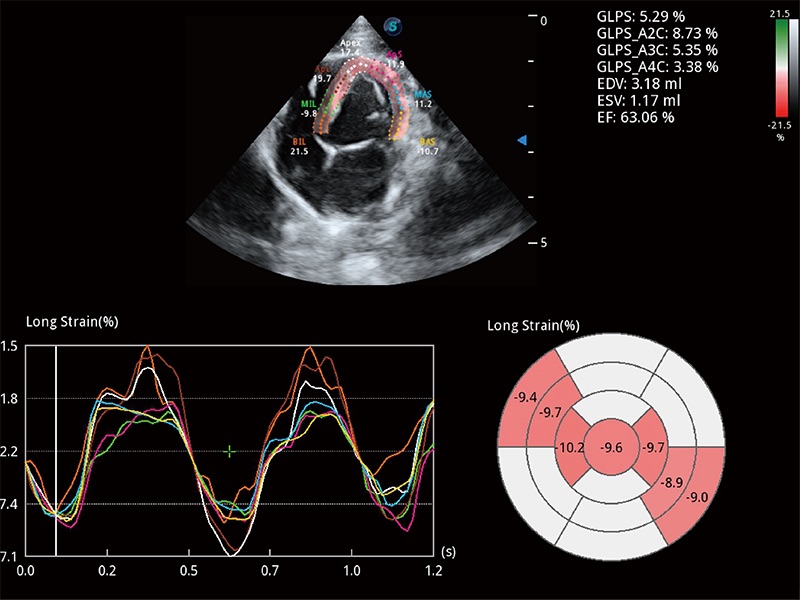

• MQA 心肌定量分析

通過心肌識別技術(shù)與二維斑點追蹤技術(shù)相結(jié)合,對心臟的超聲圖像進(jìn)行量化分析。計算心肌17個節(jié)段的應(yīng)變、應(yīng)變率、速度、位移等,并通過牛眼圖的形式進(jìn)行呈現(xiàn)。

(犬)四腔心MQA